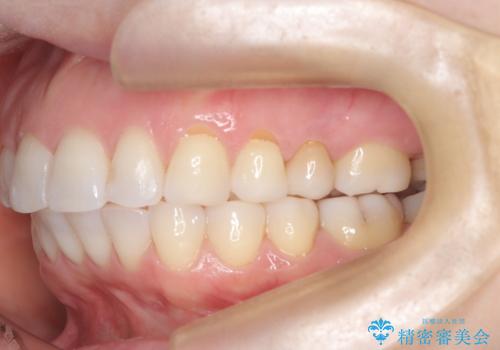

審美装置を用いたワイヤー矯正|非抜歯で歯の凸凹を改善

- 患者様は**歯の凸凹(叢生)**を気にされて来院されました。診査の結果、歯列のスペースが不足しているものの、抜歯をせずに改善できる状態でした。そこで、目立ちにくい審美装置(白いブラケットとホワイトワイヤー)を使用したワイヤー矯正を提案しました。歯列のアーチを広げながら、適宜IPR(歯の幅をわずかに調整する処置)を行い、非抜歯で自然な歯並びへと導く計画を立てました。

治療では、白いブラケットとホワイトワイヤーを使用し、矯正装置が目立ちにくいよう配慮しました。歯列を拡大しながら適切に歯を移動させ、IPRを併用することで、無理なくスペースを確保しました。見た目に配慮しながら、歯の凸凹をスムーズに整え、噛み合わせも改善。患者様からは「装置が思ったより目立たず、歯並びがきれいになって嬉しい」との声をいただきました。